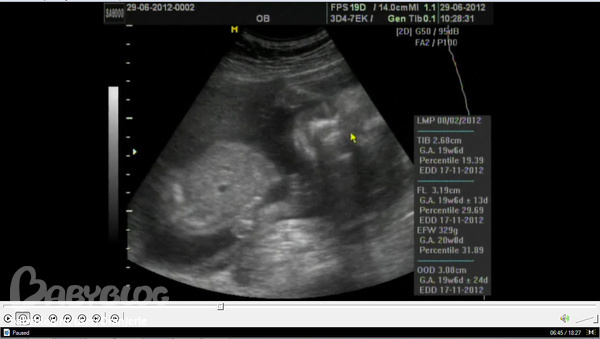

Дальше замеры-замеры: все у детки в норме, весит уже 330 грамм - кабасик))) у меня тоже все хорошо, плацента поднялась - уже 45 мм выше внутреннего зева. Единстенное, сказали, что шейка матки коротковата - 27 мм, но внутренний зев закрыт, так что ничего ( хотя на предыдущих узи на 9 и на 12 неделе она была 30 мм и на осмотре ни у врача из ЖК, ни у врача из РД никаких претензий к ее длине не было). Кровотоки все в норме.

В общем, любуюсь уже который раз видео с УЗИ. Наш мальчик-зайчик просто прелесть)) Ножки такие ням-ням, а когда пальчики растопыривает - я вообще пищу от восторга! И вот сделала принскрин, где видно его личико даже хорошо))